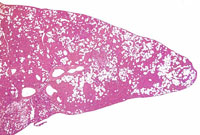

An Ito cell tumor that has replaced much of the normal hepatic parenchyma without distorting the normal contour of the liver; higher magnification shows fat-filled and stellate cells in the hepatic sinusoids.